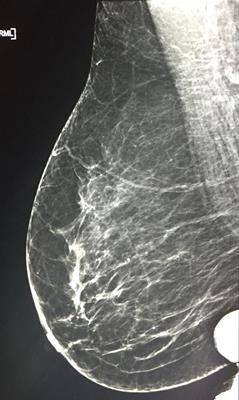

How well is mammography performed in Malta? No one knows for sure because image-quality studies haven't been conducted -- until now. New research found that the average reject rate for the nation fell within acceptable levels, but there is still room for improvement, particularly at individual centers.

A research team led by Nicole Mercieca from the medical imaging department at Mater Dei Hospital in Msida, Malta, found that the recorded average reject rate across the country for mammography images fell within acceptable levels. But calculation of reject rates at individual centers revealed unacceptable readings.

The researchers prospectively collected a total of 2,291 images over two weeks with 60 rejected images being recorded. This accounted for a national reject rate of 2.62%, which is within European mammography guidelines (less than 3%). However, analysis of the individual centers revealed rates ranging from 0.82% to 8.8%.